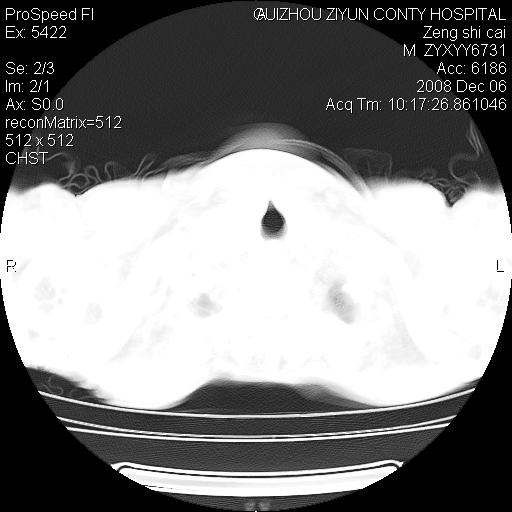

标题: CT16961:M、71岁,咳嗽半年,无血痰;胸片示右肺占位。 [打印本页]

标题: CT16961:M、71岁,咳嗽半年,无血痰;胸片示右肺占位。

右肺癌并纵隔淋巴结及胸膜转移可能性大

右肺纵隔型肺癌伴纵隔淋巴结及胸膜转移!

右肺纵隔型肺癌伴纵隔淋巴结转移!双侧胸水!

1)考虑右肺上叶纵隔型肺癌伴纵隔淋巴结转移。2)心包积液,双侧胸腔积液。

右肺上叶纵隔型肺癌伴纵隔淋巴结转移。心包积液,双侧胸腔积液。